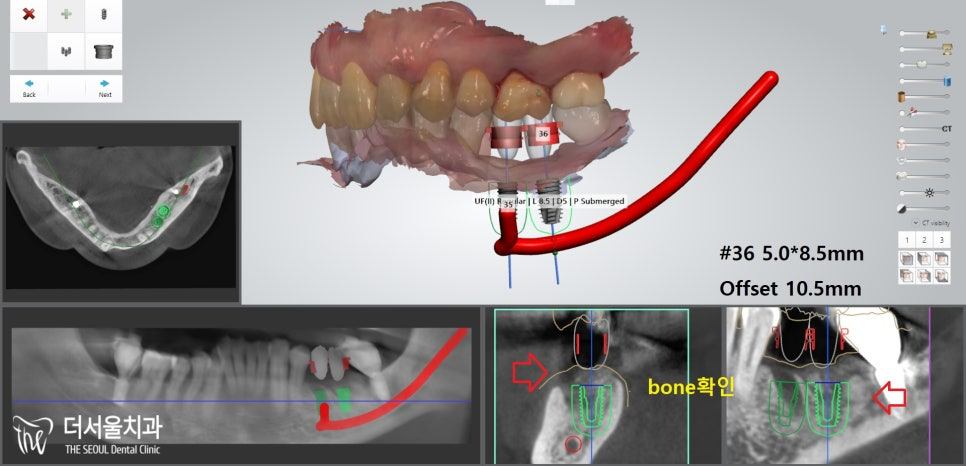

편안한 식립을 돕기 위해

컴퓨터분석임플란트 를 하기로 계획을 세웠습니다.

『컴퓨터분석임플란트 로 보다 편안하게』

컴퓨터분석임플란트 를 심기 전,

내부 조직과의 위치 관계를 확인해야겠죠?

하악은? 하치조신경관~

초록색 선이 신경관의 위치입니다.

이럴 땐 더더욱 컴퓨터분석임플란트 를 해야 됩니다.

정확한 위치 및 거리 계산을 통해

단 0.001mm의 오차도 발생하지 않도록 진행을 해야 되죠.

자칫 삐끗했다간 신경관 손상 및 마비로

이어질 수 있는 큰 문제이기 때문이죠.